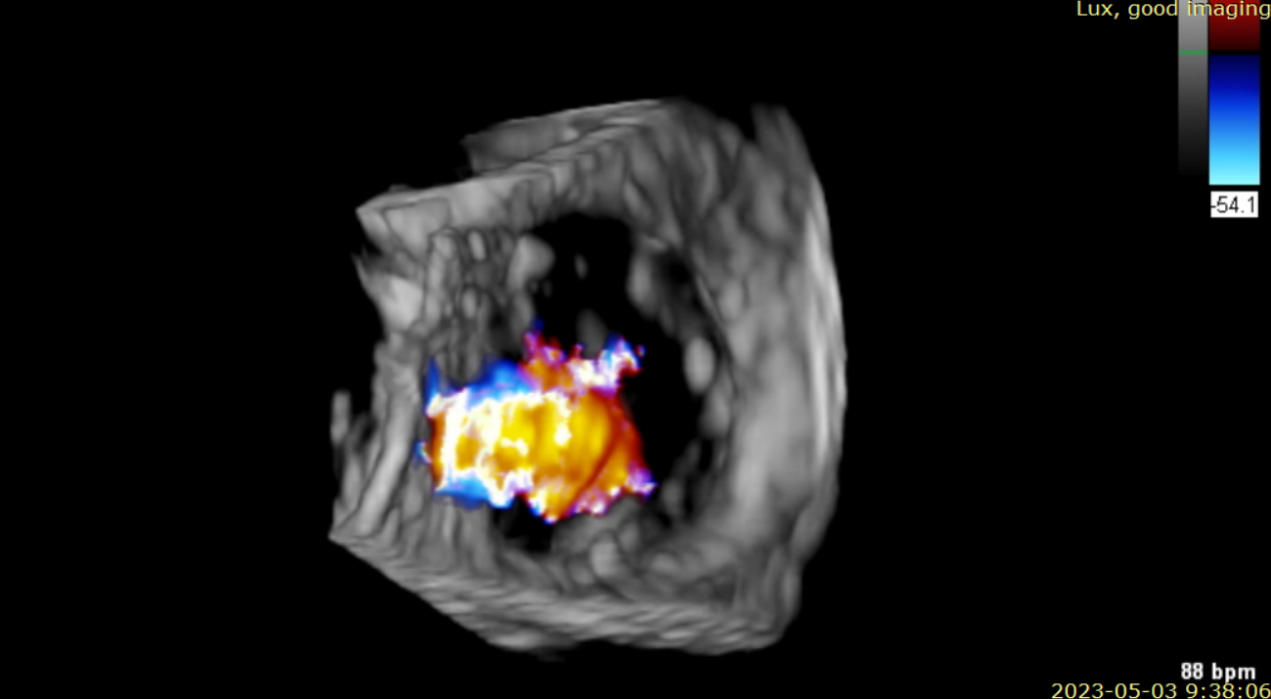

術(shù)后超聲提示無(wú)瓣周漏

術(shù)后超聲提示僅殘余輕微瓣周漏